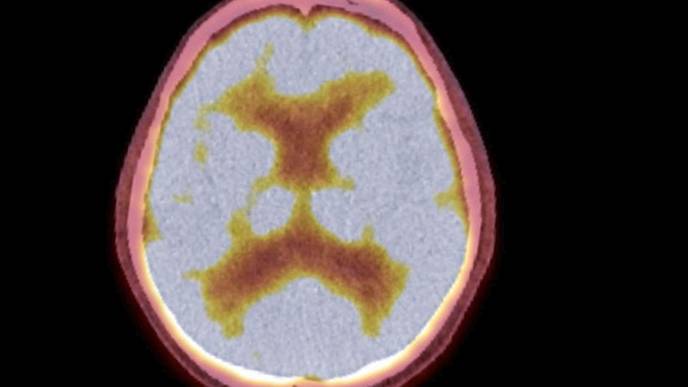

In a new study, investigators from McLean Hospital, Harvard Medical School and the National Institute on Drug Abuse—Intramural Research Program (NIDA-IRP) have discovered that the tendency of people's arousal to wane over the course of brain scans has been distorting the brain connection maps produced by functional magnetic resonance imaging (fMRI).

The team found that as people's arousal levels dwindle during an fMRI, such as if they become more relaxed and sleepy, changes in breathing and heart rates alter blood oxygen levels in the brain—which are then falsely detected on the scan as neuronal activity.

fMRI scans are commonly used to non-invasively map brain connectivity in a variety of situations, including planning for surgery, understanding the impact of a stroke, and studying how mental illness affects neurological function. However, since fMRI relies on changes in brain blood oxygen to indirectly measure neuronal activity, it is vulnerable to "noise" from other processes that can affect blood oxygen—such as changes in breathing and heart rates.

In the present study, the research team identified a specific blood flow signal that seemed to track both the decline in subject arousal levels and the illusory inflation of functional brain connection strengths. This non-neuronal, physiological noise signal—termed the "systemic low frequency oscillation" (sLFO) signal—grew over time during scanning, in a spatial and temporal pattern that tightly matched the pattern of the connection strength increases.